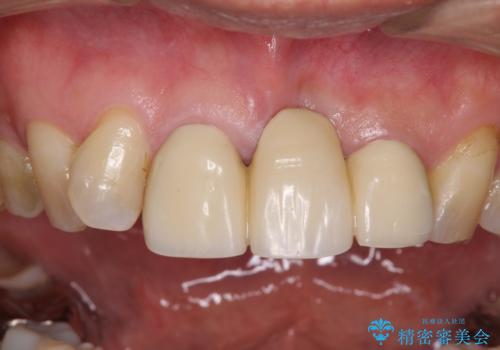

- 保険診療の前歯のブリッジが、形態も色も不自然で気になるとのことで来院された患者様です。

神経の抜かれている土台の歯は根管治療を行った上で、オールセラミックブリッジにより補綴することとしました。

術前の状態より、欠損部位には歯肉移植術が必要と思われましたが、仮歯で調整したところ自然な歯列となったため、外科処置は行わずに自然な口元に仕上がりました。